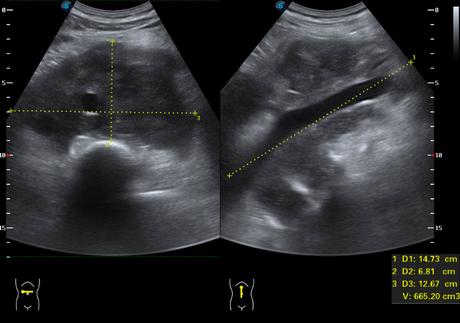

POR MEDIO PARTICULAR SE SOLICITA USG ABDOMINAL COMO ABORDAJE INICIAL. MOSTRANDO MASA RETROPERITONEAL DE GRAN TAMAÑO DE HASTA 14.7 CM, HIPOECOICA RESPECTO A LA GRASA ABDOMINAL, DE BORDES DEFINIDOS, QUE ENVUELVE LOS VASOS ABDOMINALES SIN COMPRIMIRLOS, QUE A LA EXPLORACIÓN CON DOPPLER COLOR QUE NO MUESTRA VASCULARIDAD.

MASCULINO DE 56 AÑOS CON MASA EN EPIGASTRIO A QUIEN SE LE REALIZA USG Y TAC CONTRASTADA MOSTRANDO MASA RETROPERITONEAL DE HASTA 14 CM, LA CUAL DESPLAZA LAS ESTRUCTURAS VASCULARES.